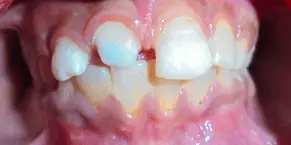

Case :6

RESTORATION OF TRAUMATIZED TOOTH BY PREFABRICATED METAL POST

A 10 yr old boy came to the department with a chief complaint of broken tooth in the upper front tooth region. On clinical examination, Ellis Class III fracture was present irt 11. Root canal therapy was performed and post space preparation was done and a prefabricated metal post was luted irt 11 and polycarbonate crown was luted.